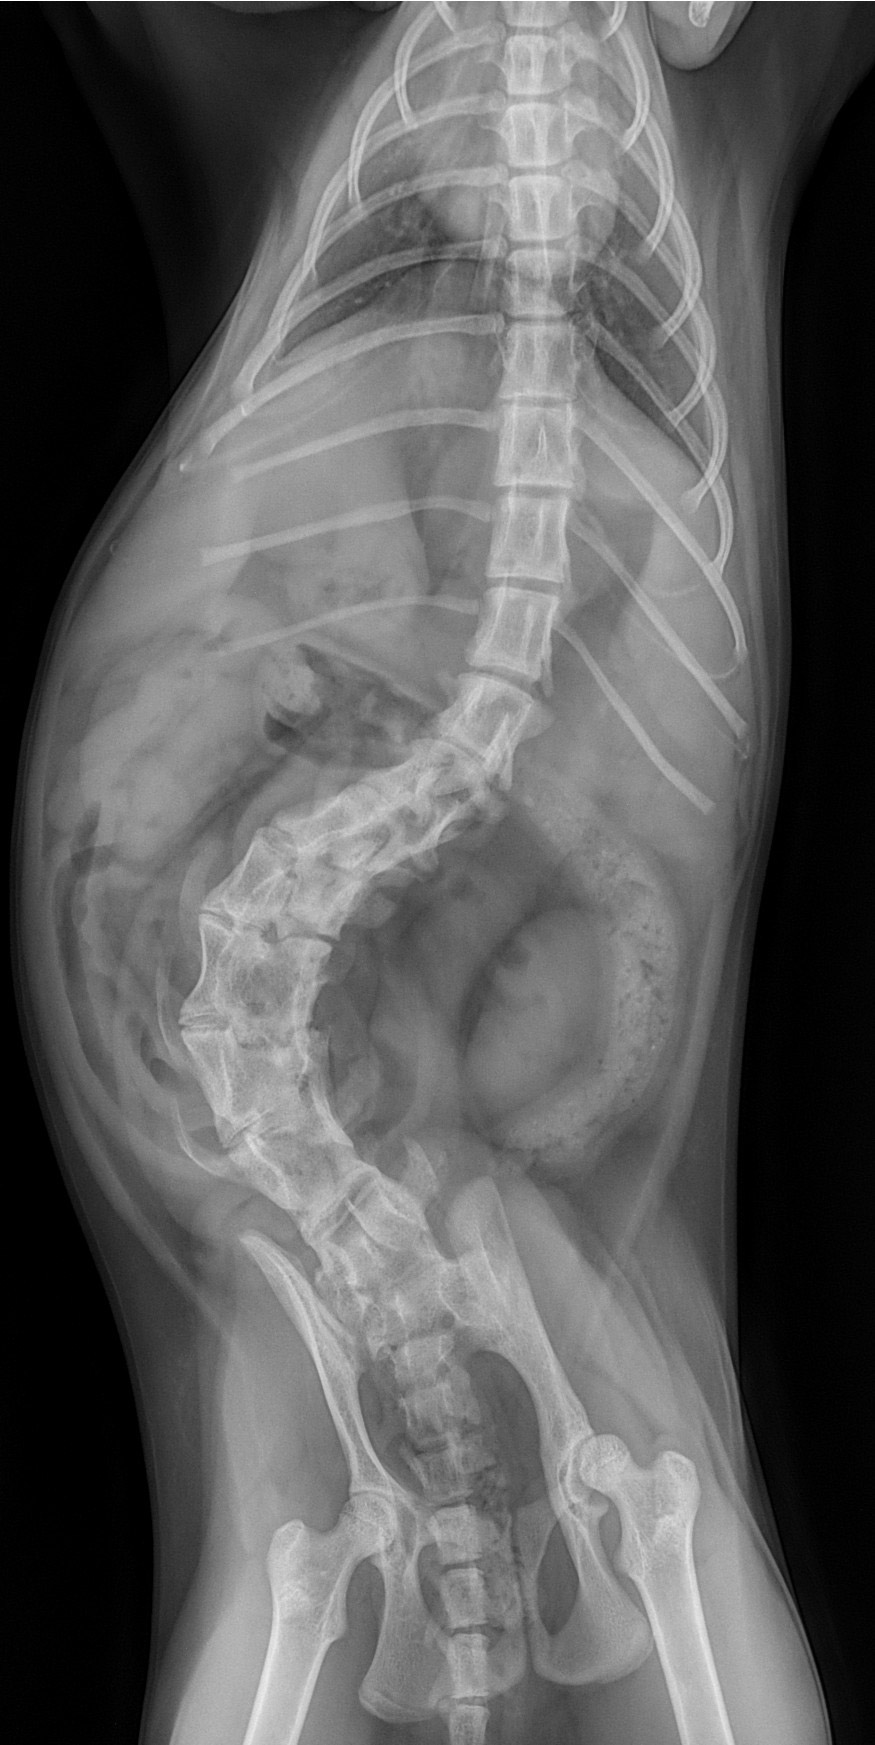

Notre service est équipé d’un scanner Canon® de dernière génération 16 barettes permettant des images haute résolution du thorax, de l’abdomen, du rachis et des articulations. Notre échographe offre une analyse fine des organes internes, du cœur et des tissus mous. Nos deux salles de radiologie numérique assurent des clichés rapides, précis et immédiatement exploitables.